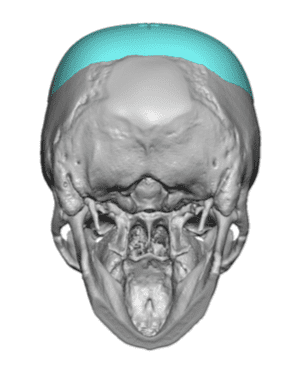

Desire for a higher and more prominent crown of the skull.

Crown of skull augmentation using a custom skull implant.

Desire for a higher and more prominent crown of the skull.

Crown of skull augmentation using a custom skull implant.